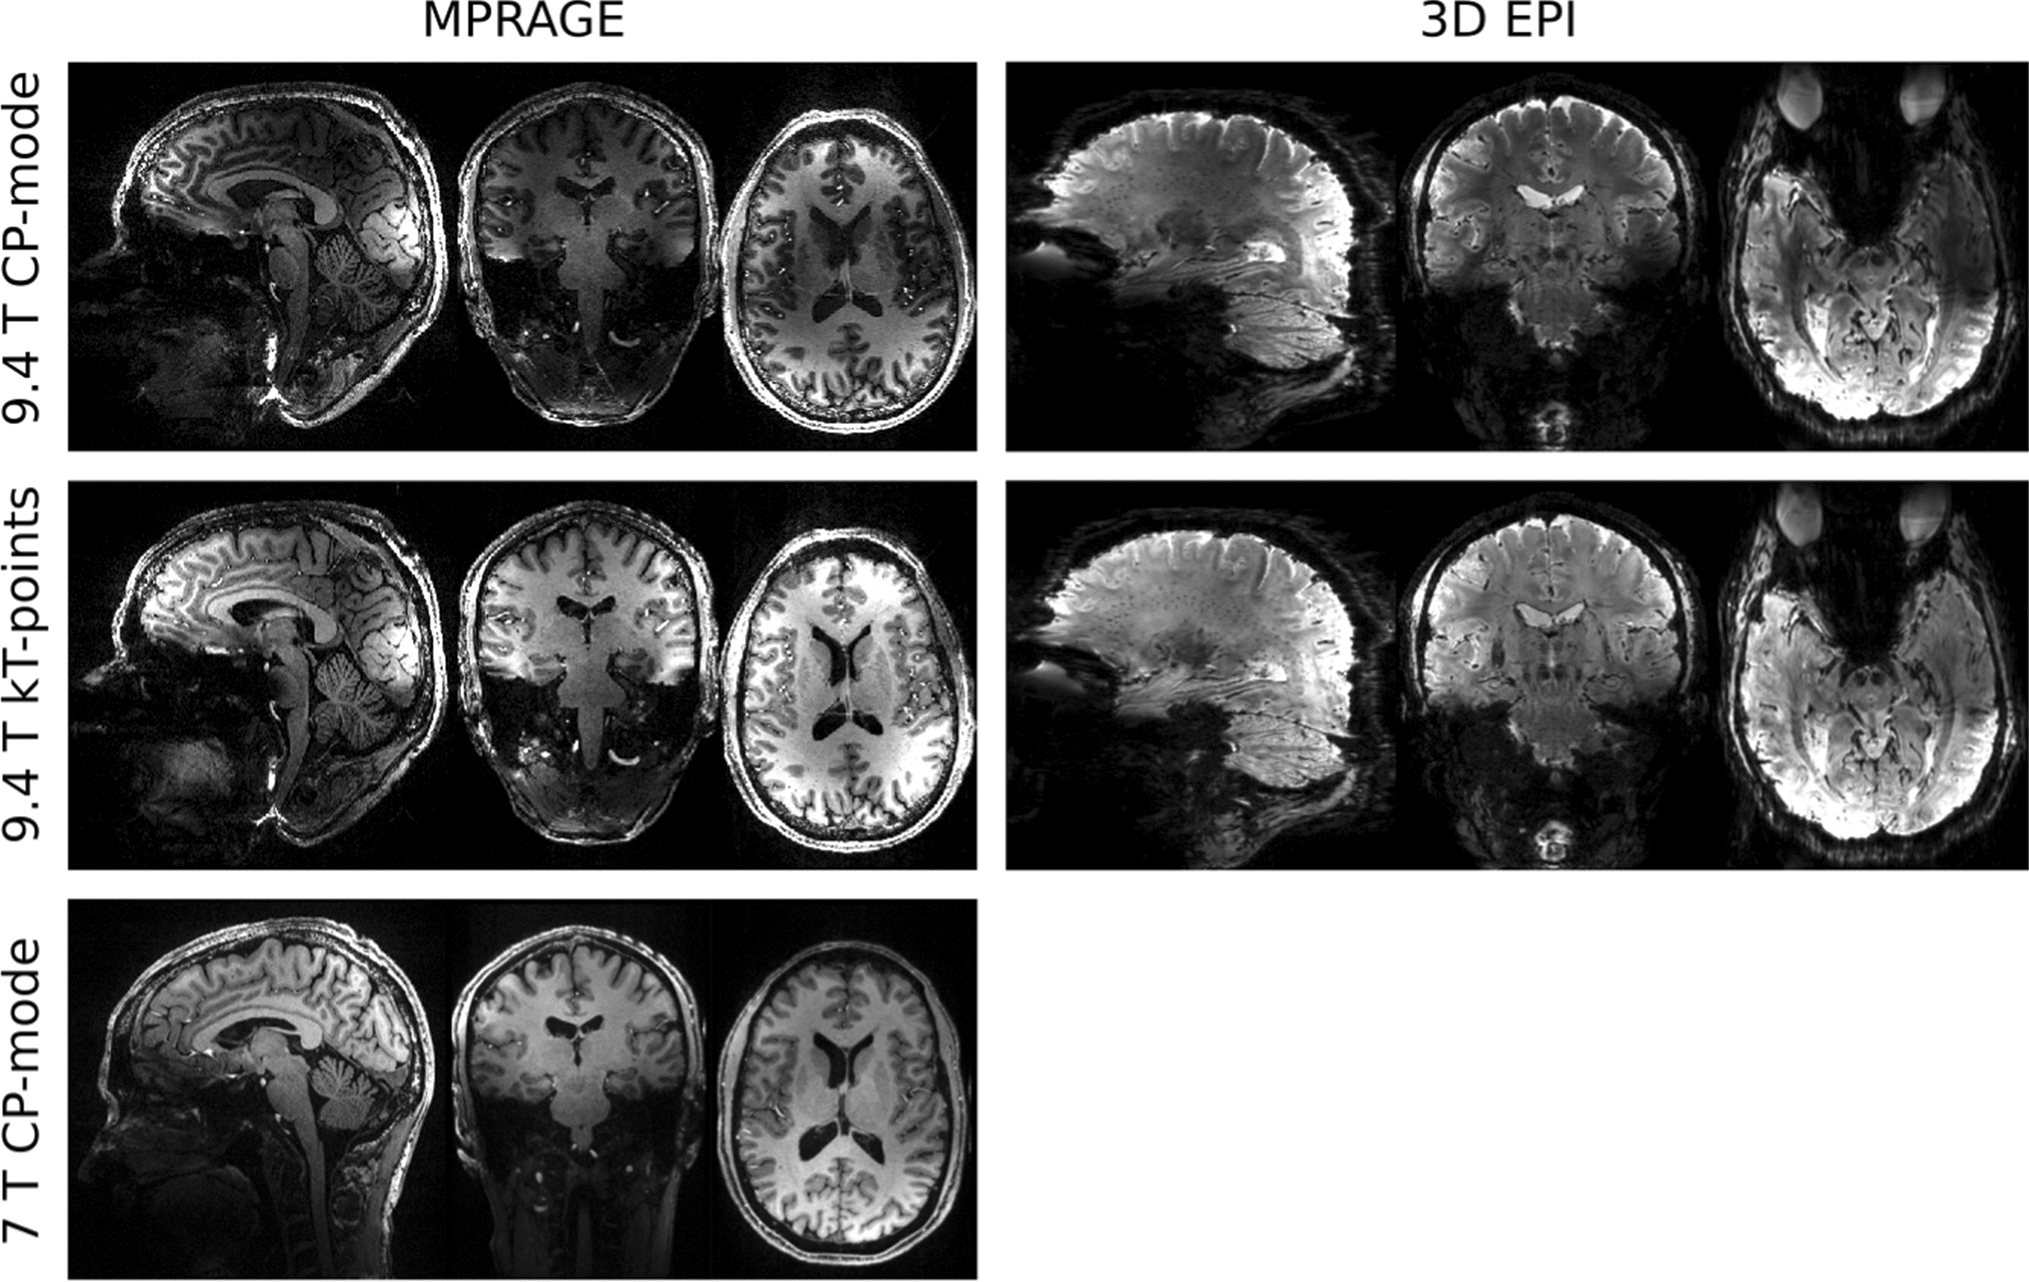

Figure 1 shows the 3D imaging examples of MPRAGE and 3D EPI using kT-points pulses. The MPRAGE scan was acquired using the following parameters: TR = 3.75 s, TE = 3.64 ms, TI = 1.2 s, matrix size 384 × 384 × 256, voxel size 0.6 mm isotropic, sagittal slices and anterior-to-posterior phase encoding direction, slice partial Fourier 7/8, echo train length = 2.1 s, flip-angle = 5 degrees, GRAPPA factor 3 along the in-plane phase encoding direction with 24 reference lines, bandwidth 180 Hz/pixel. The total scan duration was 8:58 min. The inversion pulse employed was TR-FOCI [46]. The same kT-points excitation was also applied in the 3D EPI sequence [47] with parameters as follows: TR = 61 ms, effective volume TR = 12.7 s, TE = 22 ms, matrix size 256 × 256 × 208, voxel size 0.75 mm isotropic, phase partial Fourier 6/8, flip-angle 15 degrees, bandwidth 1396 Hz/pixel, and GRAPPA factor 3 along the in-plane phase encoding direction using 96/48 reference lines/partitions that were acquired in a segmented lines-in-partition order [48]. The total acquisition time was 1:28 min. For a visual comparison, the same images acquired without parallel transmission pulse, i.e. in CP mode, are also shown in Fig. 1, middle row. Finally, an MPRAGE of the same participant with matched acquisition parameters was acquired at our 7 T in combined (CP) mode using the 1 Tx/32 Rx Nova Medical (Wilmington, MA, USA) RF head coil. The direct comparison between the MPRAGE images demonstrates the exacerbation of both the transmit and receive B1 inhomogeneity at 9.4 T compared to the 7 T.

Fig. 1

MPRAGE (0.6 mm isotropic resolution) and 3D EPI (0.75 mm isotropic resolution) images, obtained using CP-mode (top row) and kT-points (middle row) excitations. MPRAGE (0.6 mm isotropic resolution) from the same participant acquired using the 1Tx/32Rx Nova Medical head coil at 7 T (CP-mode)